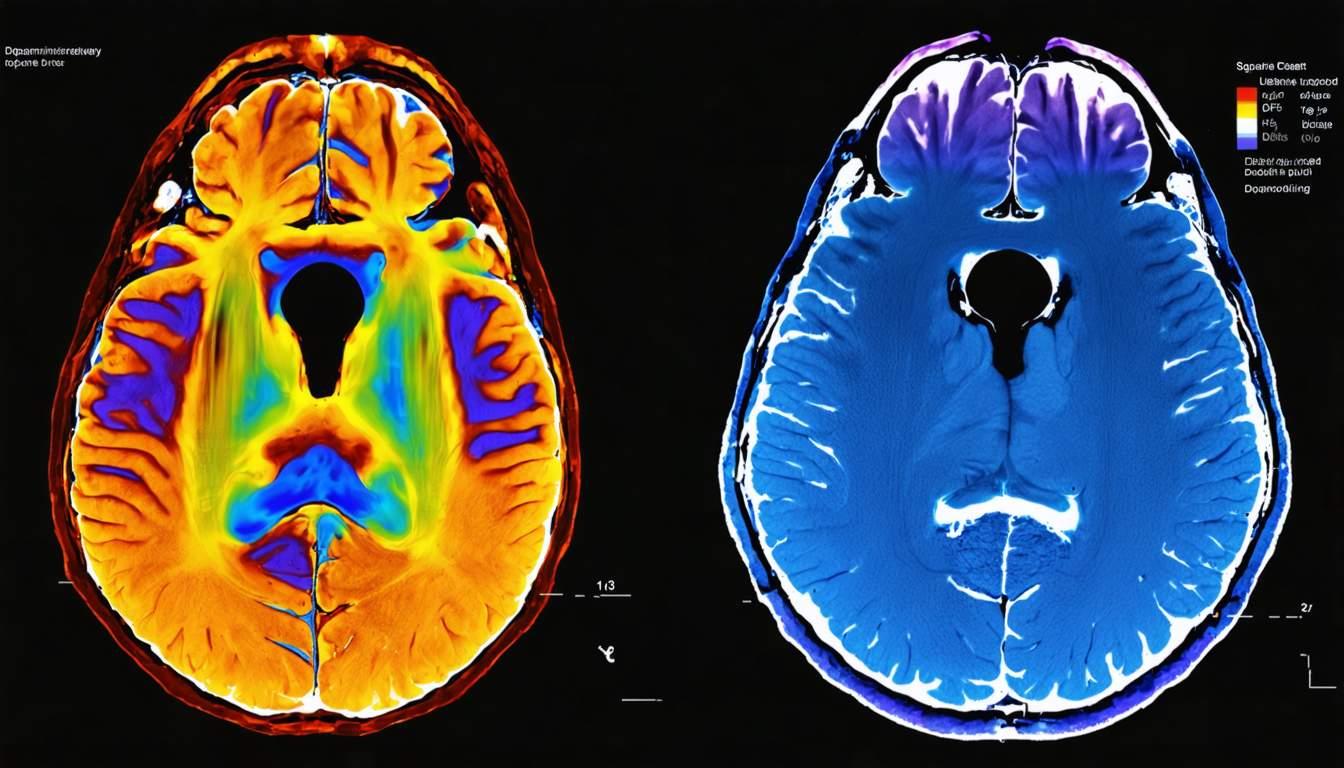

DaTSCAN and PET imaging are advanced diagnostic tools used to differentiate and assess movement disorders such as Parkinson’s disease and atypical parkinsonism.

DaTSCAN (Ioflupane I-123 SPECT) is primarily used for differentiating Parkinsonian syndromes from essential tremor. It assesses dopamine transporter (DAT) availability in the basal ganglia.

- Interpretation: Reduced DAT uptake in the striatum suggests neurodegeneration

PET (Positron Emission Tomography) utilizes radiotracers to assess metabolic activity and neurotransmitter function.

- Types: FDG-PET (metabolic imaging), F-DOPA PET (dopaminergic function assessment)

- Advantages: High sensitivity and specificity